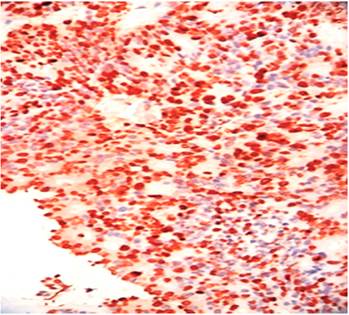

La colonoscopia reveló una lesión de aspecto tumoral a nivel de la válvula ileocecal, redondeada de unos 4 cm de tamaño y del mismo color que la mucosa circundante; se apreció el signo de la tienda de campaña, que es la elevación de la pared intestinal con base ancha y vértice romo, sin pedículo con conservación de la mucosa intacta (Figuras 3 y 4). Se tomó una biopsia para el estudio histológico, que informó la presencia de un carcinoma neuroendocrino poco diferenciado grado III. La inmunohistoquímica fue positiva a enolasa neuroespecífica (NSE), sinaptofisina y Ki 67 (Figuras 5, 6 y 7).

El diagnóstico de esta entidad debe incluir determinaciones de 5-HT en orinas de 24 horas para los carcinoides productores de serotonina, la cual no fue posible realizar por dificultades con el estudio. La TAC y resonancia magnética nuclear (RMN) han demostrado poseer similitud para el diagnóstico de metástasis regionales y a distancia con un 77 % y un 80 %, respectivamente 7; en este paciente, la TAC con doble contraste fue muy efectiva; y fue igualmente útil la endoscopia digestiva, el tránsito intestinal y el ultrasonido abdominal. Para mejorar el diagnóstico de esta entidad se usa una serie de marcadores de inmunohistoquímica, entre ellos la ENS y los marcadores asociados con vesículas pequeñas (sinaptofisina). Hay una relación casi lineal entre el tamaño y la presencia de metástasis, el 85 % de los tumores de más de 2 cm produce metástasis 5, comprobado en este paciente.